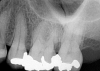

The patient presented with temperature sensitivity and pain during mastication (Figure 3). Local anesthesia was delivered, and steps 1 through 4 were performed.

Fig 3. Preoperative maxillary left bicuspid.

Figure 3